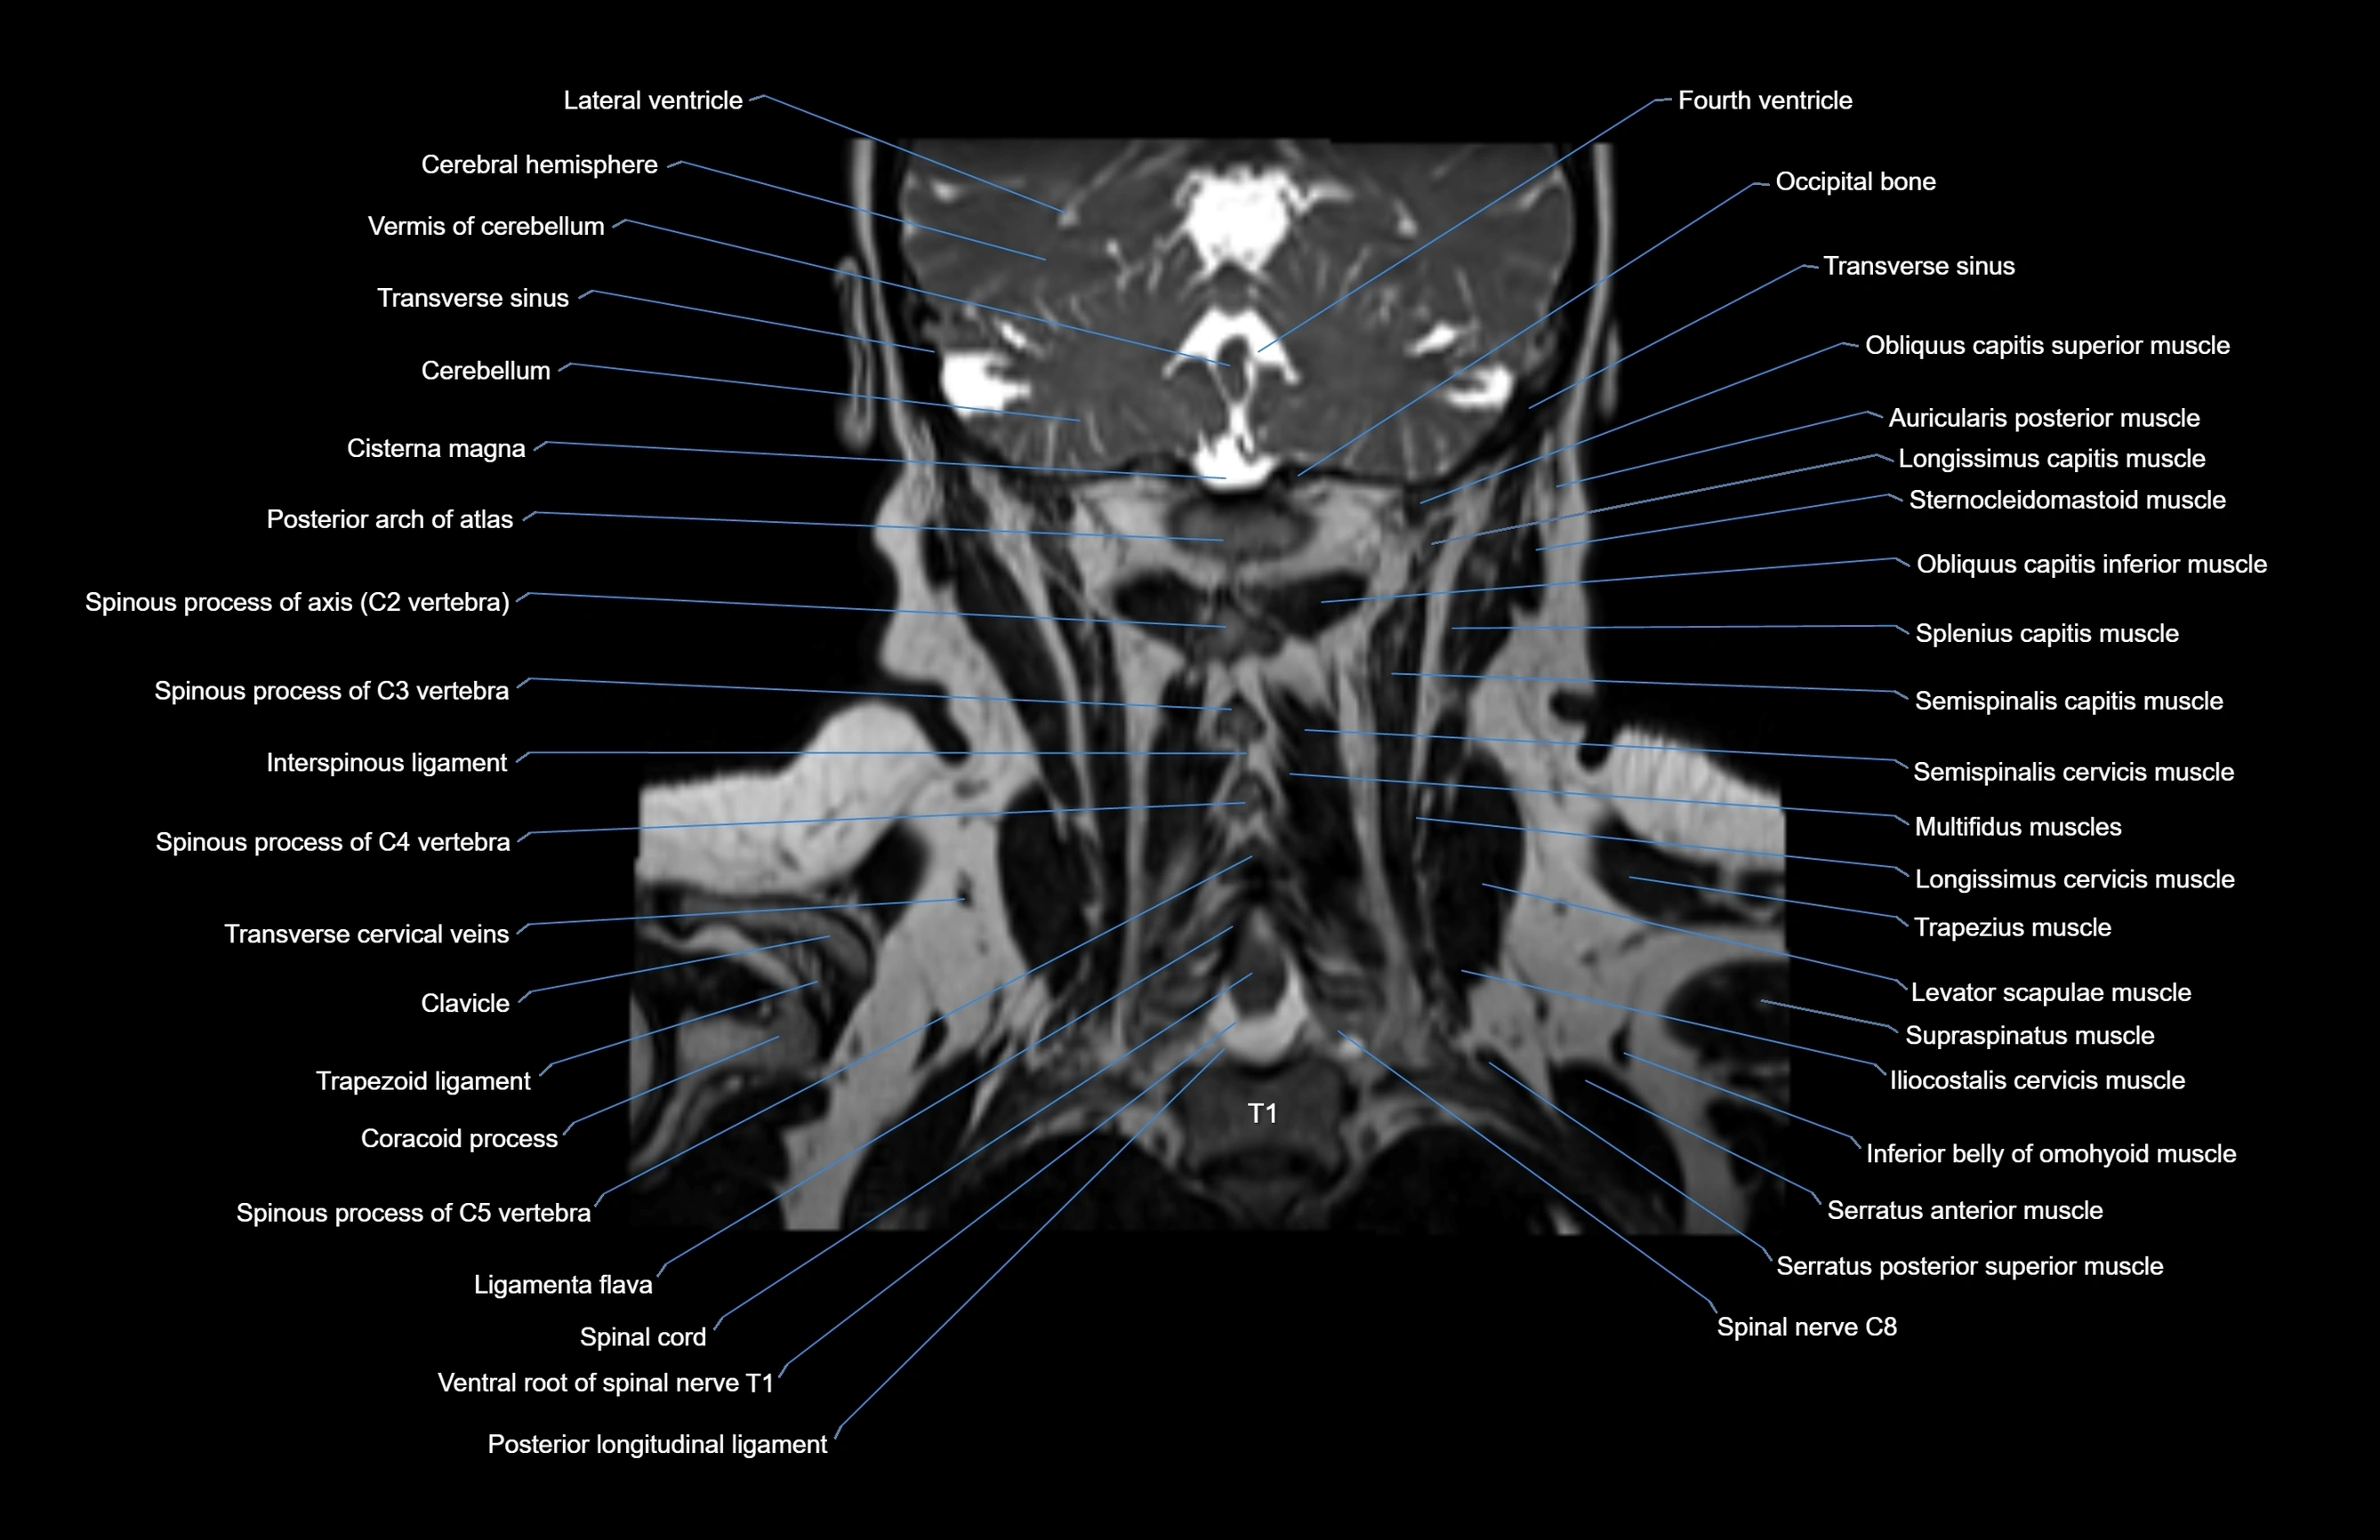

MRI images